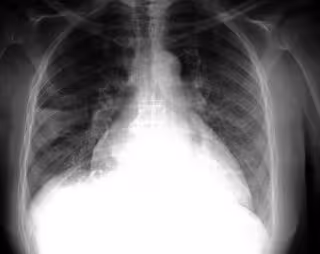

Foto: FLICKR/PULMONARY PATHOLOGY/CC BY-SA 2.0

En concreto, señalan desde Seram, la radiografía de tórax es una prueba complementaria que en la actualidad se realiza de forma rutinaria en la valoración preoperatoria de los pacientes. "Se trata de una

prueba que irradia de forma innecesaria a los pacientes y no aporta información relevante al anestesista", advierte el informe.